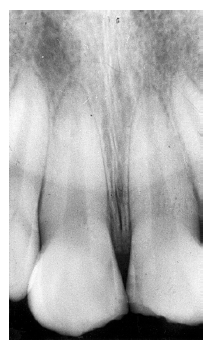

Figure 13 - Apical Periodontal Pathosis

Figure 13

The periapical granuloma represents the body’s defense mechanism attempting to wall off irritants draining from a non-vital dental pulp. While they cannot be radiologically differentiated from abscesses or cysts, they can be differentiated from normal anatomical landmarks such as the incisive fossa because the periodontal ligament space is widened and the lamina dura is not continuously intact.

Figure 13 illustrates apical periodontal pathosis in the area of the right central incisor. Note the loss of continuity of the lamina dura and the widened periodontal ligament space on the affected side.